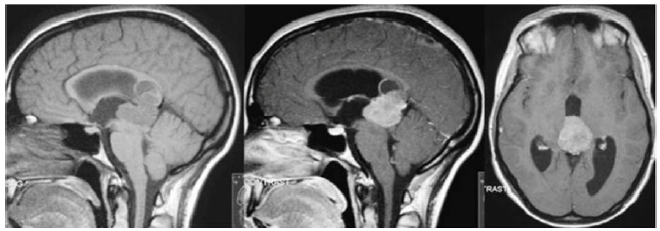

Um paciente de 28 anos de idade, previamente hígido, queixa-se de cefaleia de intensidade progressiva há duas semanas, associada a vômitos e à turvação visual. Ao exame físico, observa-se sonolência e desorientação, bem como papiledema à fundoscopia, paresia do olhar conjugado para cima e nistagmo em convergência. Traz consigo a ressonância magnética de crânio mostrada a seguir, que foi realizada após pedido de médico no posto de saúde.

enunciado 323575-1

O diagnóstico mais provável para esse caso hipotético é o de

enunciado 323463-1

Além da síndrome de hipertensão intracraniana, outra síndrome observada no quadro clínico do paciente é a de